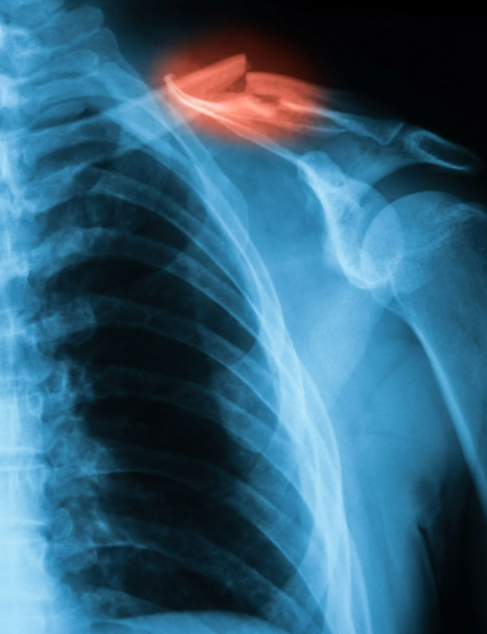

▣ 어깨는뼈는 크게 3가지입니다.

어깨 상완골(긴팔뼈)

쇄골

견갑골

▣ 석회 성 건염

석회 성 건염의 원인을 확인할 수는 없지만 상당히 고통스러울 수 있습니다. 칼슘 침착 물이 근육이나 힘줄에 축적되는 상태로 석회 성 건염을 설명합니다. X- 레이로 볼 수 있으며 일반적으로 30세 이상이지만 모든 연령에서 발생할 수 있는 사람들에게 더 흔합니다.